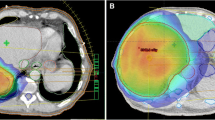

Maximum dose delivered to the heart (mean 25.3 Gy vs. 24.5 Gy, p = 0.048) and ribs (mean 38.7 Gy vs. 37.7 Gy, p = 0.044) was significantly higher for simple IMRT (figure 3) but no other statistically significant differences were seen in other OARs, liver Veff, biological liver NTCP or mean liver dose. Examples of simple IMRT and index IMRT plans are shown in figure 4.

Axial (left panels) and Coronal (right panels) slices of acceptable index and simple IMRT, showing the six fraction, lowest isodose covering 0.5 cc PTV (orange), the 30 Gy isodose (dark blue) and 10 Gy isodose (beige) surrounding the PTV (pink colorwash). Examples are shown of a small lesion typical of liver SBRT (A), where loss of dose conformation of higher isodoses may have larger effects on normal tissue function, as compared to a larger lesion near bowel treated to lower doses (B).

RTOG CI was significantly higher (poorer dose conformity) for simple IMRT than index IMRT (mean 1.52 vs. 1.42, p = 0.001, figure 5a) with similar differences for plans with prescription dose ≥ 42 Gy (mean 1.33 vs. 1.45, p = 0.026) or < 42 Gy (mean 1.52 vs. 1.60, p = 0.007), demonstrating reduced conformality in the simple IMRT plans. This was also reflected in larger isodose volumes outside PTV for 42 Gy (mean 74 vs. 63 mL, p = 0.025), 30 Gy (mean 364 vs. 323 mL, p = 0.003) but not for 1 Gy (mean 8220 vs. 8271 mL, p = 0.517) or integral dose (69.1 J vs. 68.7 J (p = 0.374)). Using multivariable linear regression, the sole factor that statistically correlated with a higher RTOG CI in simple and index IMRT was number of tumours in the liver (p = 0.004, adjusted R2 = 0.26 and p = 0.047, adjusted R2 = 0.115 respectively) as seen in figure 5b.